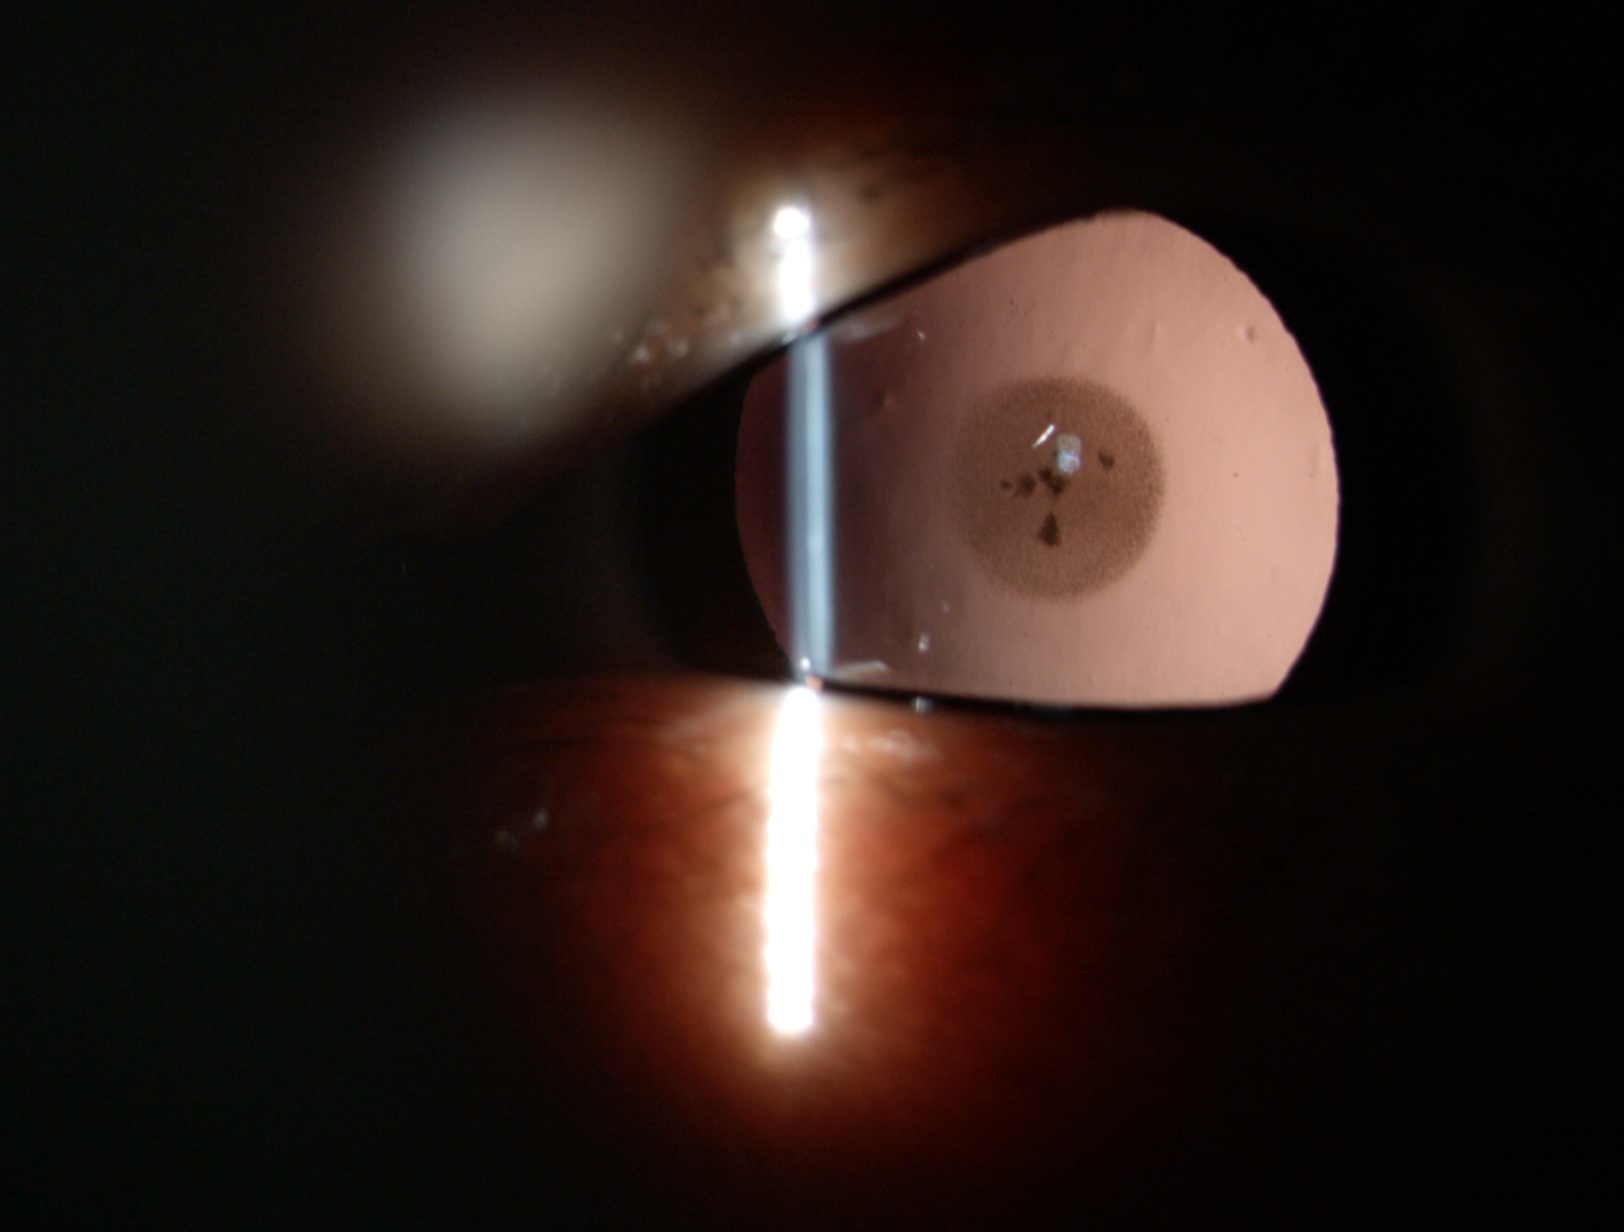

白內(nèi)障的手術(shù)效果好與不好

目前,沒有特效藥治療白內(nèi)障,即便有的藥物對(duì)早期的白內(nèi)障可起到緩解癥狀的作用,但無法逆轉(zhuǎn)病情,手術(shù)是治療白內(nèi)障有效的方法,通過將混濁的晶體蛋白清除,換上透明的人工晶狀體,才能讓白內(nèi)障患者重獲清晰視力。

白內(nèi)障的手術(shù)效果好與不好,主要與以下幾個(gè)因素有關(guān)。

白內(nèi)障癥狀

現(xiàn)在白內(nèi)障手術(shù)都是微創(chuàng)手術(shù),當(dāng)然是手術(shù)切口越小手術(shù)引起的散光越小,對(duì)視力影響也越小。做手術(shù)的超乳設(shè)備穩(wěn)定性越好手術(shù)越順利,出現(xiàn)不必要并發(fā)癥的概率就越小,人工晶體檢查計(jì)算設(shè)備也是非常重要的,直接影響術(shù)后視力,常規(guī)眼球一般經(jīng)典的A/B超和角膜曲率也是比較準(zhǔn)的。